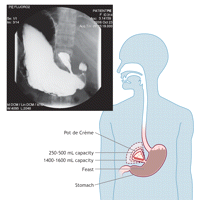

Results A hollow pouch extruding from the stomach antrum was observed in all plates (100%) made using Fudge-o-grafin, but in none (0%) made using barium sulfate as the contrast agent. Eighteen of 25 subjects (72%) complimented the flavour, smooth texture and pleasant aftertaste of the Fudge-o-grafin and 1 (4%) requested more with which to wash down the post-test pie. The pouch was found to vary only in size. In 5 cases (20%) pouch volume was estimated to be 150–250 mL. In 18 cases (72%) the volume was estimated to be 250–500 mL, while in the remaining 2 cases (8%) the volume was estimated to be an exceptional 1400–1600 mL. Each outpouching was shaped like a slice of pie, with the apex located at the antrum. The wall of the outpouching in each case was 5–6 mm in thickness, with rugae protruding into the lumen of the pouch at regular intervals of 8–9 mm. Interpretation This radiographic study clearly demonstrates the presence of a previously undescribed anatomic phenomenon, to be known hereafter as the “Pot de Crème.” The claim that dessert simply “fills in the cracks” has been absolutely refuted. In retrospect, the idea that “cracks” could exist between boluses of well-masticated food seems absurd. This discovery is significant in and of itself. However, the questions raised by the presence of a pouch are perhaps even more important to our understanding of anatomy and physiology. First, is this pouch a genetic gift to a select few, or is it an endowment to all that undergoes atrophy in children without access to sufficient quantities of cookies, creams and chocolates? Second, Fudge-o-grafin may contain the key to an as yet undiscovered neurohormonal circuit, the details of which may be of commercial interest and are awaiting clarification. Footnotes Conflicts of interest: The authors have interests in both chocolate and pie, and sometimes have conflicting thoughts about what to have for dessert."